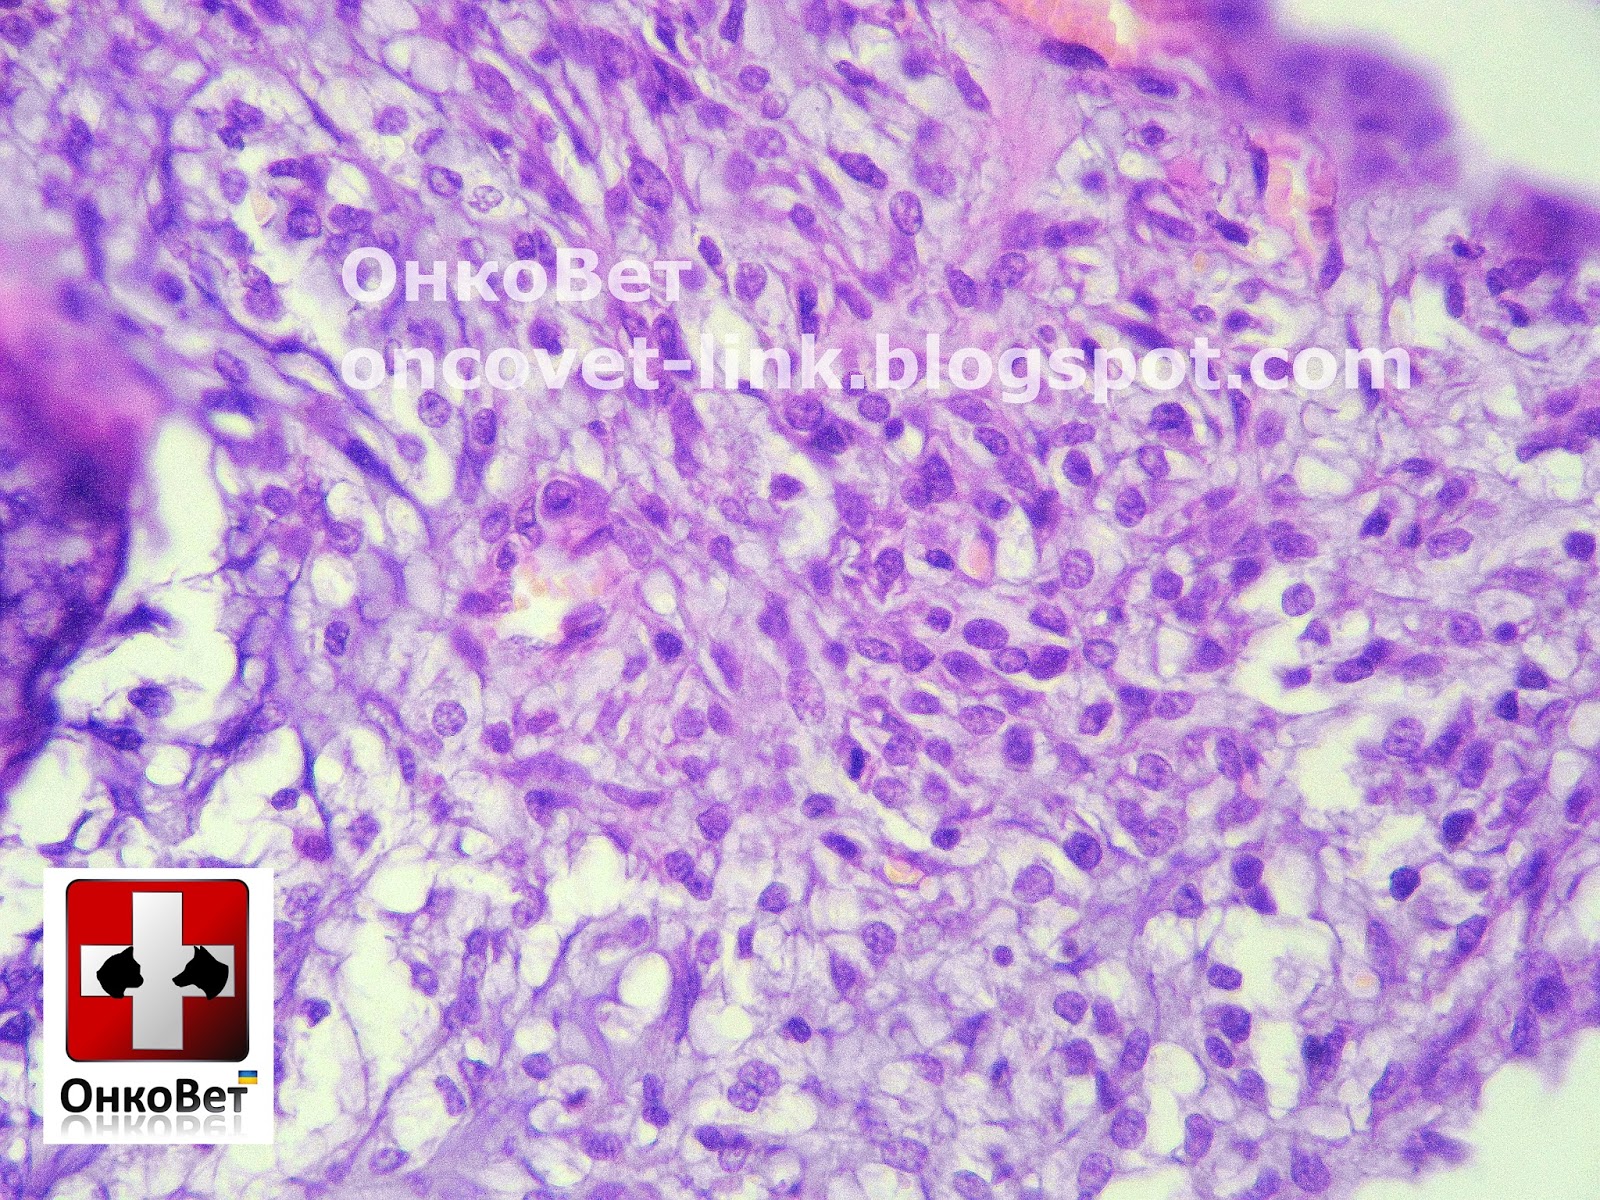

Медицинские исследования: гистология эозинофильного энтерита